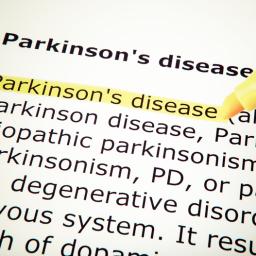

So… to start with, I’m Tom, and you can find out more about me using the ‘About‘ item on the right side on my blog home page. In this blog I am going to talk about a number of different topics, but the two biggest will be #1: my journey with Parkinson’s Disease (PD). And #2: since I just retired from being a computer programmer (for 38 years!) I’ll be throwing in some technical stuff here and there also. And who knows? Along the way I might thrown in a few other odds and ends (and some humor as well).

First off, Parkinson’s – Yes, I unfortunately have it, and am now an official ‘Parkie’!